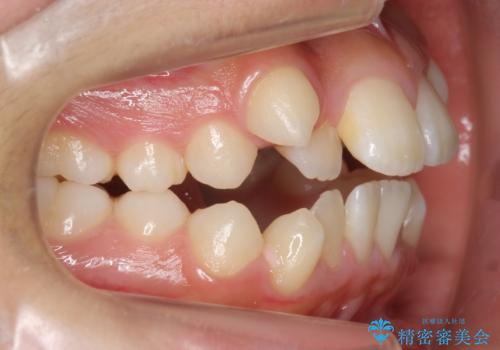

八重歯や、前歯のオープンバイト(開咬)の症状があり、マウスピース(インビザライン)矯正単独では治すのが難しい症状が複合していました。

八重歯や抜歯したスペースの閉鎖をワイヤー矯正で前半行い、治療後半は目立たないインビザラインでかみ合わせを調整しました。